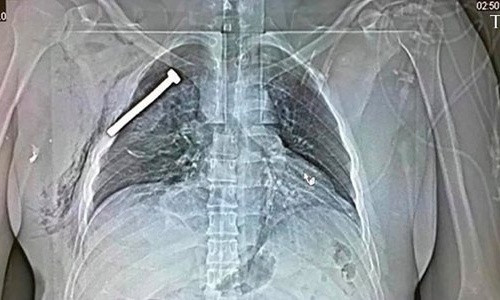

Ảnh chụp X-quang của một nạn nhân cho thấy một chiếc đinh lớn nằm trong lồng ngực người này. Ảnh: EPA

Theo một quan chức y tế Brussels, các quả bom còn nhồi đầy đinh. Đây là cách mà những kẻ chế tạo bom thường dùng để gia tăng tối đa mức độ sát thương.

"Bom chứa đinh sẽ tạo ra nhiều thương vong hơn. Một số nạn nhân đã bị đinh găm sâu vào cơ thể", Marc Decramer, người phát ngôn Bệnh viện Đại học Gasthuisberg ở Leuven, nói. Ảnh chụp X-quang của một nạn nhân cũng cho thấy một chiếc đinh lớn nằm trong lồng ngực người này.